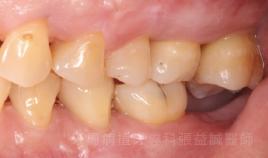

治療前 治療後

治療前

治療後